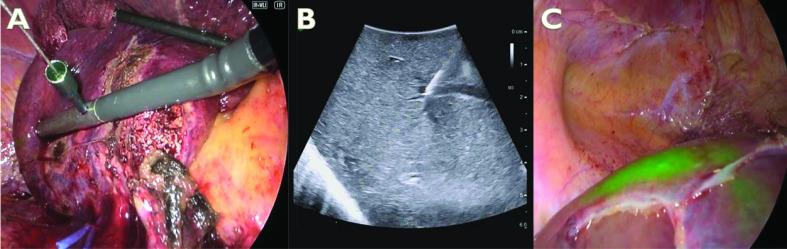

This is a prospective randomised controlled superiority clinical trial performed in a single centre tertiary hospital in Japan. A comparison between the accuracy of positive and negative ICG staining in guiding laparoscopic anatomical liver resection is planned in this study. Possible candidates are patients with liver malignant tumours in whom laparoscopic monosegmentectomy or subsegmentectomy is planned. Fifty patients will be prospectively allocated into the following two groups: group A, ICG-negative staining group, and group B, ICG-positive staining group. The optimal dose of ICG for positive staining will be determined during the preparation phase. To assess the ability of the ICG fluorescence guidance in anatomical resection, the primary endpoint is the success rate of ICG staining, which consists of a SOS based on three components: superficial demarcation in the liver surface, visualisation of the parenchymal borders and consistency with the preoperative three-dimensional simulation. The secondary endpoints are the evaluation of short-term surgical outcomes and recurrence-free survival.

这是一项在日本一家单中心三级医院进行的前瞻性随机对照优效性临床试验。本研究计划比较 ICG 阳性和阴性染色在指导腹腔镜解剖性肝切除中的准确性。可能的候选者是计划行腹腔镜单段或亚段切除术的肝脏恶性肿瘤患者。50 名患者将前瞻性分配到以下两组:A 组,ICG 阴性染色组;B 组,ICG 阳性染色组。在准备阶段将确定 ICG 阳性染色的最佳剂量。为了评估 ICG 荧光引导在解剖性肝切除中的能力,主要终点是 ICG 染色成功率,它基于三个组成部分的 SOS:肝表面的浅层边界、实质边界的可视化和与术前三维模拟的一致性。次要终点是评估短期手术结果和无复发生存率。